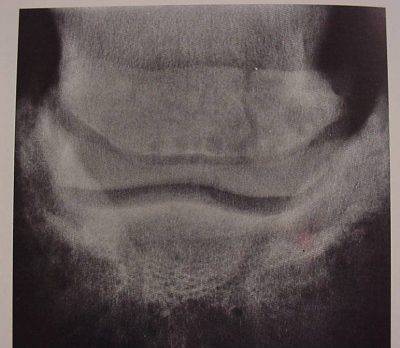

Una forma concava o “ondulata”(frequente nei cavalli da sella europei) . Nei cavalli finlandesi e frisoni la forma tende ad essere convessa. L’osso navicolare (la sua fibrocartilagine) subisce alterazioni degenerative legate all’invecchiamento (faccia palmare). Forze fisiologiche possono portare a un rimodellamento dell’osso subcondrale con ispessimento della corticale. Forze NON fisiologiche (quali-quantitative) possono portare a sclerosi e aree localizzate di lisi. L’edema, la congestione e la fibrosi dello stroma midollare può determinare la formazione di aree similcistiche.